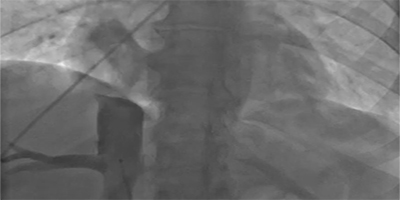

Ablation of Idiopathic Premature Ventricular Arrhythmias Originating from the Basal Cardiac Crux Region: A Case Report